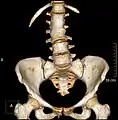

Lumbarization and sacralization

Lumbarization of sacral vertebra 1, seen as 6 vertebrae that do not connect to ribs.

Lumbarization is an anomaly in the spine. It is defined by the nonfusion of the first and second segments of the sacrum. The lumbar spine subsequently appears to have six vertebrae or segments, not five. This sixth lumbar vertebra is known as a transitional vertebra. Conversely the sacrum appears to have only four segments instead of its designated five segments. Lumbosacral transitional vertebrae consist of the process of the last lumbar vertebra fusing with the first sacral segment. [1] While only around 10 percent of adults have a spinal abnormality due to genetics, a sixth lumbar vertebra is one of the more common abnormalities. [2]